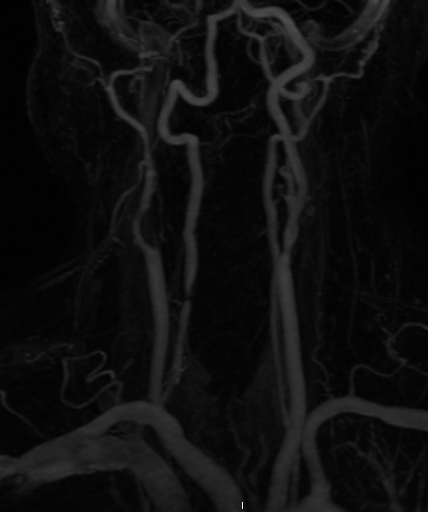

Stenosis Vertebral Artery

Photos of Stenosis Vertebral Artery

Pictures of Stenosis Vertebral Artery

Images of Stenosis Vertebral Artery

Stenosis Vertebral Artery Photos

Stenosis Vertebral Artery Images

Stenosis Vertebral Artery Pictures